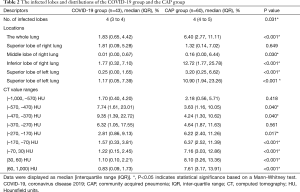

After a deep examination of false positives and negatives of the AI-enabled segmentation results and the insufficiently segmented regions, final segmentation masks were confirmed by 3 experienced radiologists and human auditing (Figure 2). The quantitative CT measurements were obtained and are set out in Table 2. The results showed that the numbers of infected lobes were significantly lower in the COVID-19 group [median (IQR): 4 (3 to 4)] than the CAP group [4 (4 to 5)] (P=0.031) Concerning the percentage of lung involvement in the whole lung, that of the CAP group was significantly more elevated than that of the COVID-19 group [median (IQR): 1.83% (0.65%, 4.42%) vs. 6.40% (2.77%, 11.11%); P<0.001]. Similarly, the percentage of lung involvement per lobe was significantly higher in the CAP group than the COVID-19 group, except for that of the right upper lobe [1.81 (0.09, 5.28) for the COVID-19 group vs. 1.32 (0.14, 7.02) for the CAP group; P=0.649].

Full table

We also investigated the percentage of lung involvement in varying CT attenuation value ranges and observed that the highest proportion of lesions in the COVID-19 group were in the CT value of (–470, –370) HU, and of (30 to 60) HU in the CAP group. Significant differences were observed between the 2 groups for all CT value ranges (P<0.05) except for the range of (–370, –270). As Table 3 shows, we also investigated the intra-class correlation coefficient (ICC) statistics between the segmentation results (infected volume fractions) derived from DL alone and human auditing. The results showed that there was good consistency in the volume proportion of the total lung infection between the groups (Table 3).

Full table

Previous studies have employed subjective evaluations using a scoring system rated by radiologists to assess disease severity (15-17). However, this semi-quantitative approach often suffers from inaccuracy and inconsistency among different readers. Additionally, it is difficult to make findings based on visual interpretations of images alone due to the disease’s lack of specificity (18,19). As our results showed, patients in the CAP group had a significantly higher lung involvement percentage in both the whole lung and individual lobes (except for the right upper lobe) than those in the COVID-19 group. Conversely, their corresponding distributions across the HU spectrum differed significantly. A higher proportion of infected lesions were found in the low-density range (–570, –270) in the COVID-19 group than the CAP group, and lung involvement peaked at higher CT value ranges (–270, 60). As different CT values represented different types of lesions (20), the results suggest that a lower density of GGO was more common in the COVID group than the CAP group, which presented with lesions of higher density.